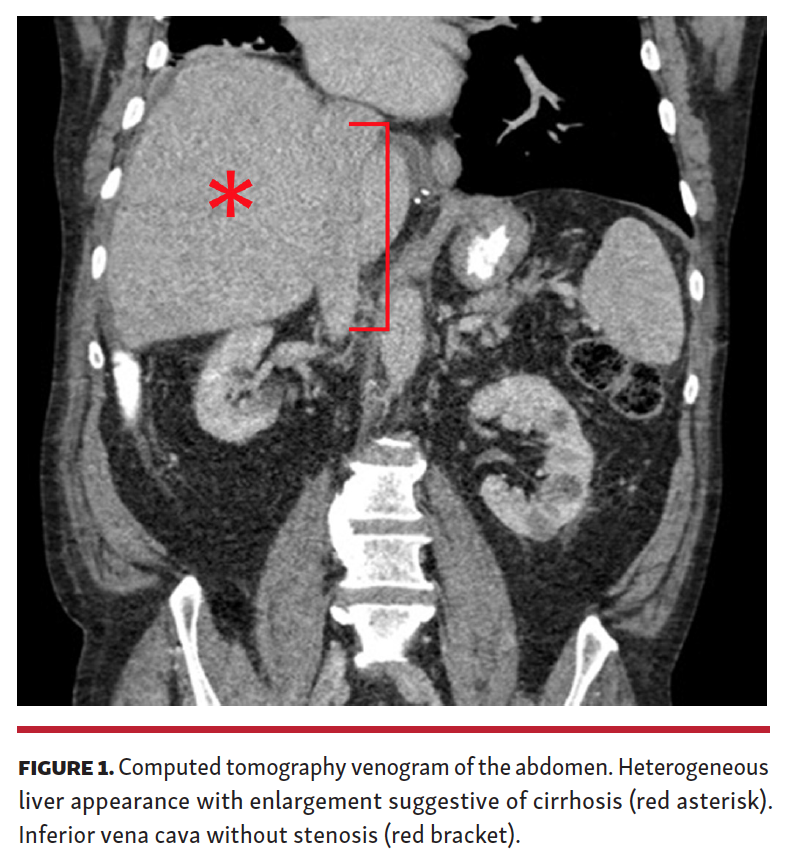

A transjugular liver biopsy and portal pressure measurements were recommended. Mean right atrial (RA) pressure was 16 mm Hg, and mean IVC and free hepatic vein pressures were 21 mm Hg, while mean hepatic vein wedge pressure was 24 mm Hg (Figure 2 and Figure 3). Because no significant gradient should be present across either the superior or inferior cavoatrial junction, we performed IVC angiography. This showed severe narrowing of the cavoatrial junction (Figure 4). Histologic examination of the liver biopsy tissue showed centrilobular sinusoidal dilation and perisinusoidal fibrosis, consistent with venous outflow obstruction (Figure 5). The patient subsequently underwent IVC balloon angioplasty with resolution of the RA-IVC gradient (Figure 6) and without caval or atrial injury.

IVC stenosis is a rare complication of bicaval orthotopic heart transplant. IVC stenosis can occur at either the cavoatrial anastomosis or the caval cannulation site, with presentations ranging from acute shock early post transplant to a more indolent course. Causes include extensive hemostatic suturing, fibrous contraction, and donor-recipient size mismatch. Treatment strategies include percutaneous balloon angioplasty (Figure 7), stenting (Figure 8), and surgical revision. Evaluating for IVC stenosis is recommended for unexplained lower extremity edema, new-onset ascites, or liver abnormalities after bicaval heart transplant.